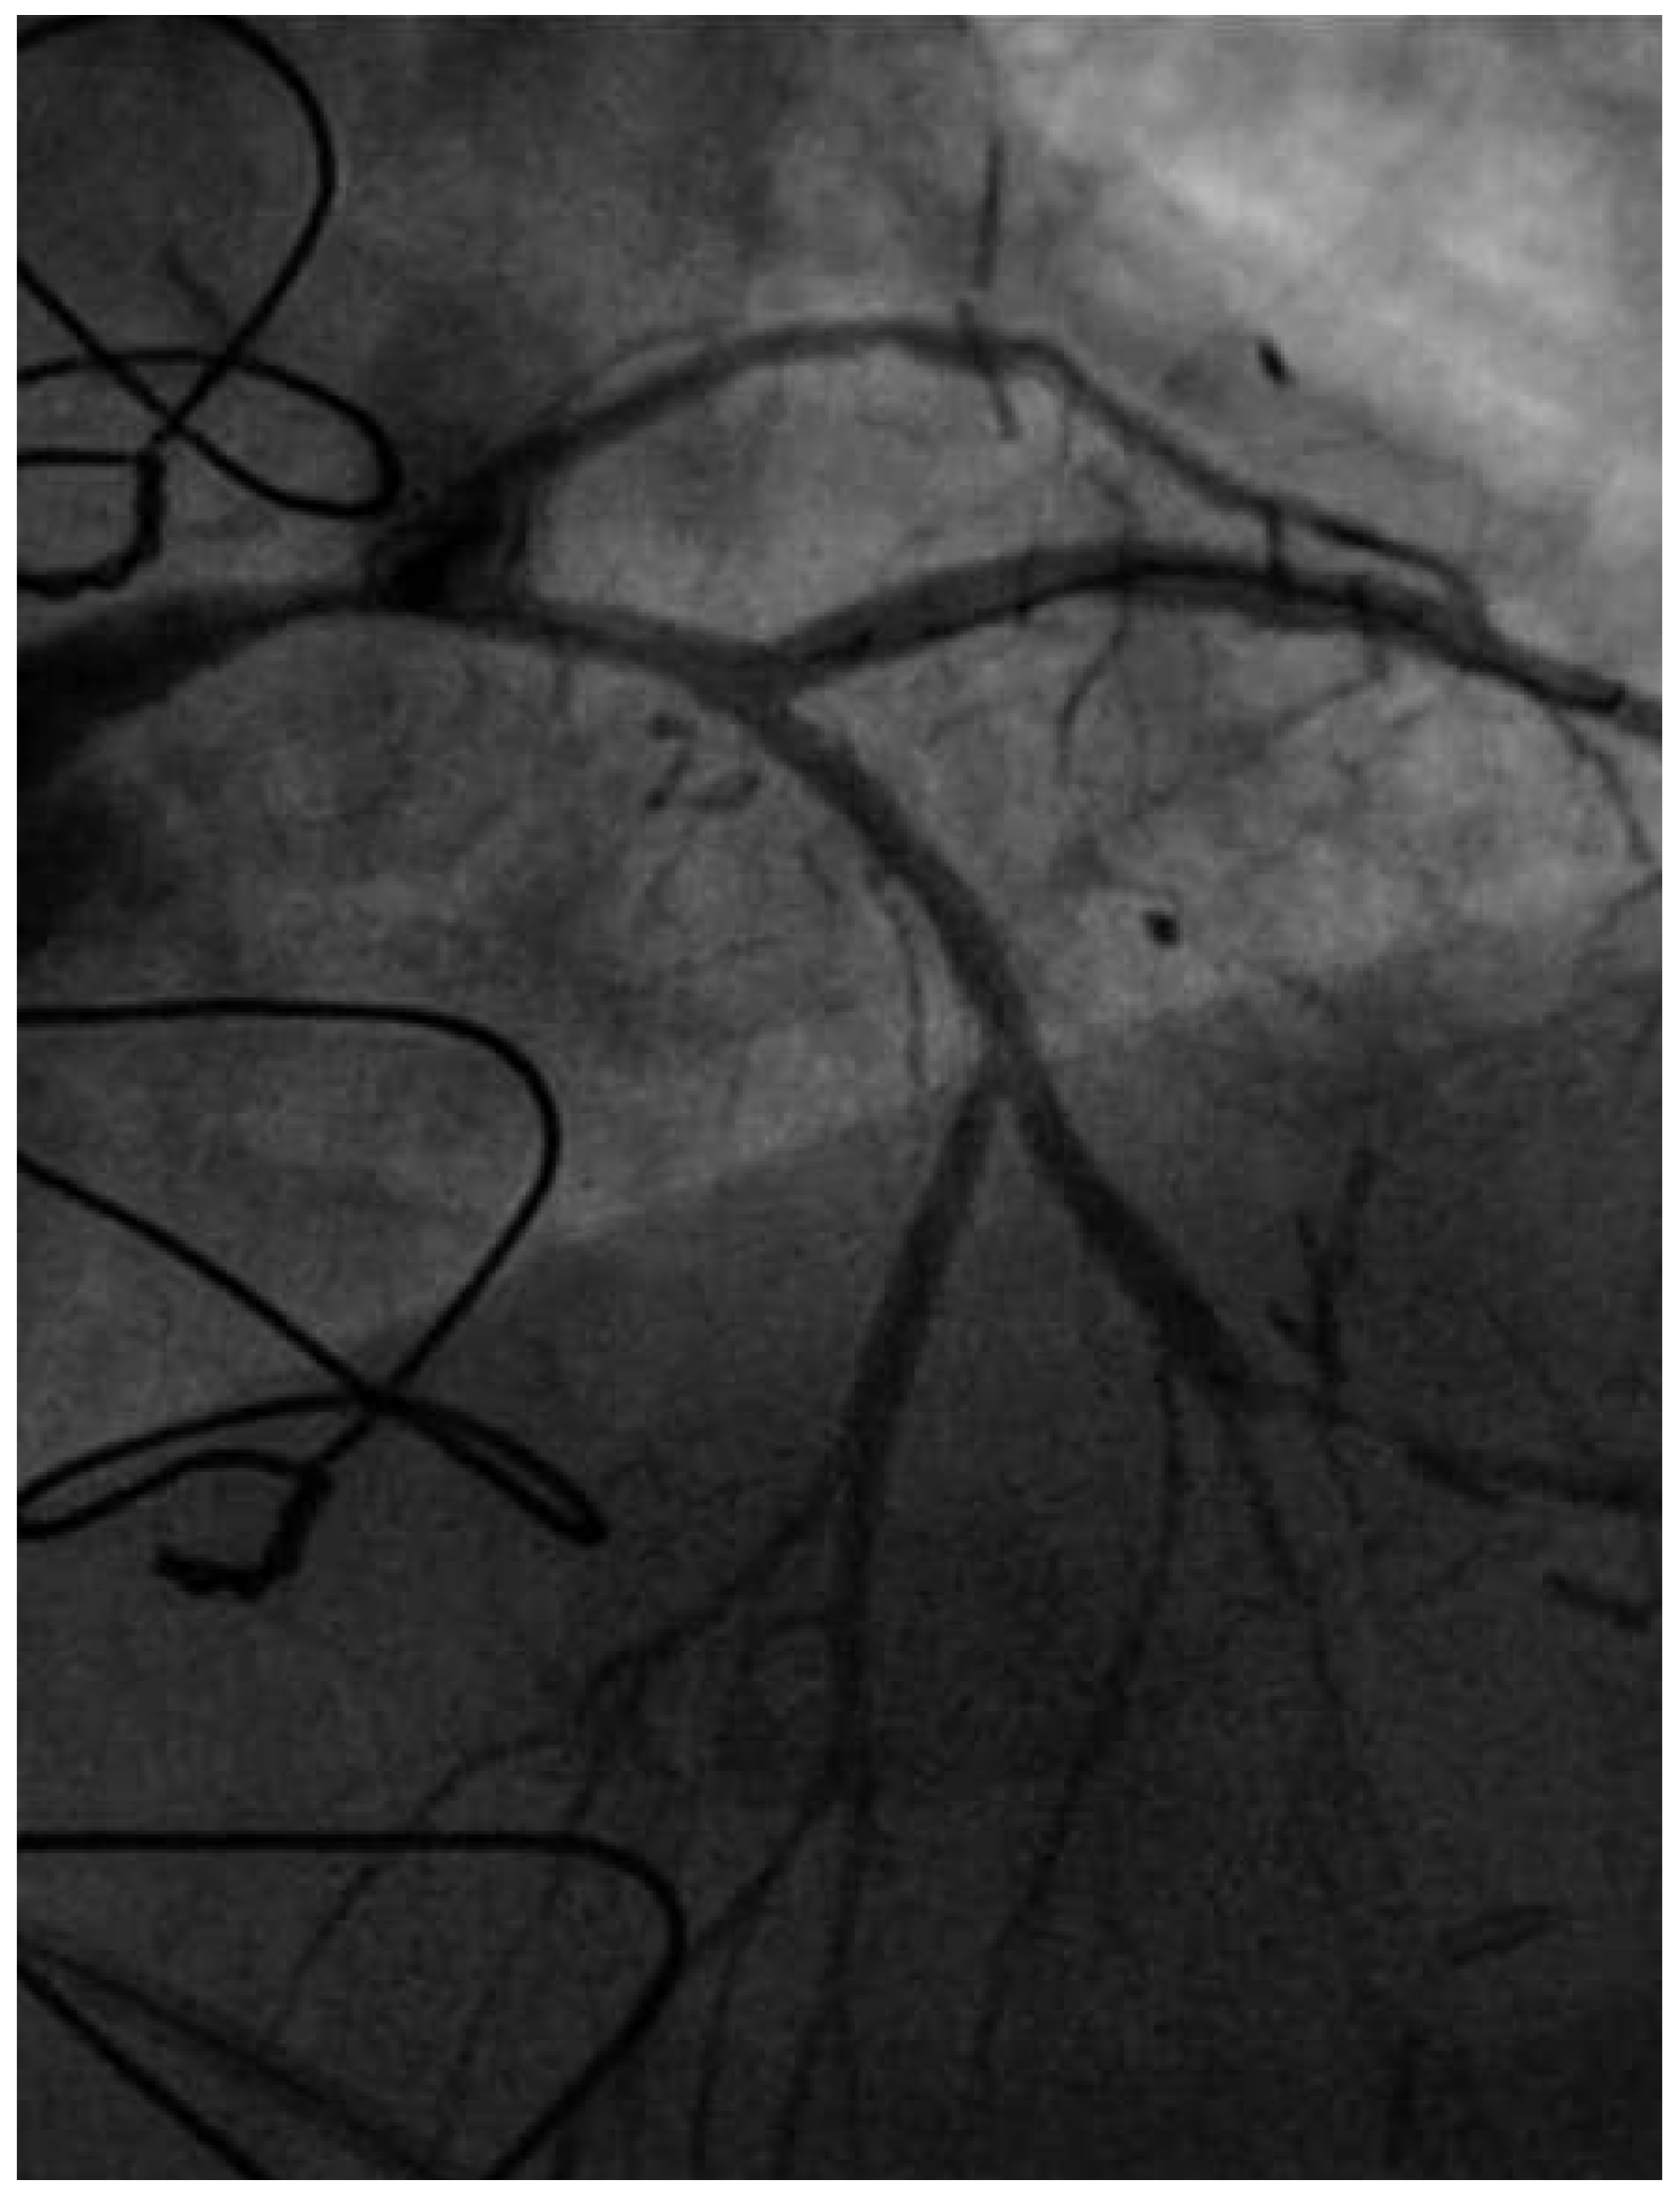

Following RA, both LAD and diagonal were wired with ease using separate Runthrough (Terumo, Japan) wires. Predilatation of both bifurcation limbs was undertaken using 1.5 × 15 mm Trek (Abbott) and 2.0 × 10 mm Sapphire (Orbus-Neich, Hong Kong, China) semicompliant balloons, which both expanded well at nominal pressure. Intending to perform an elective T-stent strategy, a 2.25 × 28 mm Promus Premier DES was deployed at 18 Atm in the diagonal branch, landing proximally at the ostium of this vessel (Figure 3). After removal of the diagonal wire, a 3 × 38 Promus Premier stent (Boston Scientific) was sited from the origin of the LMS across the first diagonal and deployed at 18 Atm (Figure 4). The diagonal branch was then rewired with the runthrough wire. A kissing inflation was performed at 12 Atm using a 3.5 × 12 Quantum (Boston Scientific) and 2.5 × 12 Sapphire noncompliant (NC) balloons in LAD and diagonal, respectively (Figure 5A). The proximal LAD and LMS were then optimised using the 3.5 Quantum NC (LAD) and a Hiryu (Terumo) 4 × 10 NC (LMS) balloons at 22 and 18 Atm, respectively (Figure 5B). The final angiographic result was excellent (Figure 6). Intravascular ultrasound of the LMS was not undertaken as angiographically the LMS stent already appeared completely expanded and oversized. We opted not to intervene in the ostial left Cx in order to best preserve the geometry of the LMS stent.

Figure 3. RAO 15°, cranial 40° view. The diagonal now stented with a Promus Premier 2.25 × 28.